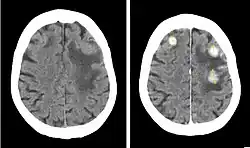

Iodinated contrast is a form of water-soluble, intravenous radiocontrast agent containing iodine, which enhances the visibility of vascular structures and organs during radiographic procedures. Some pathologies, such as cancer, have particularly improved visibility with iodinated contrast.